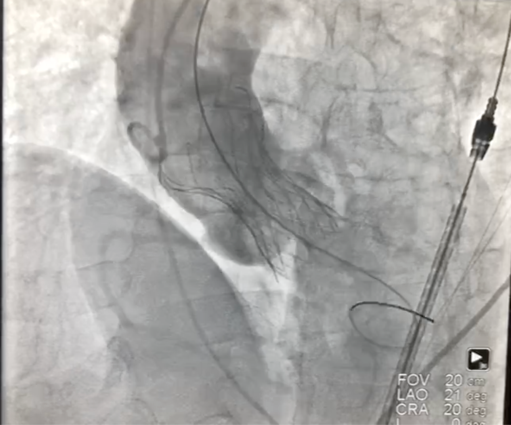

3、按照既定策略,选择24 mm VitaFlow微创瓣膜,于180 bpm快速起搏下,快速一次性释放。

4、术后心电监护未见传导阻滞,心超提示人工主动脉瓣工作良好,瓣叶启闭正常,主动脉瓣峰值流速2 m/s,平均跨瓣压差6 mmHg,轻度瓣周漏。

主动脉根部造影示瓣膜位置合适(深度2 mm),轻度瓣周漏。遂释放瓣膜,撤回脑?;ぷ爸茫质踉猜晒?。